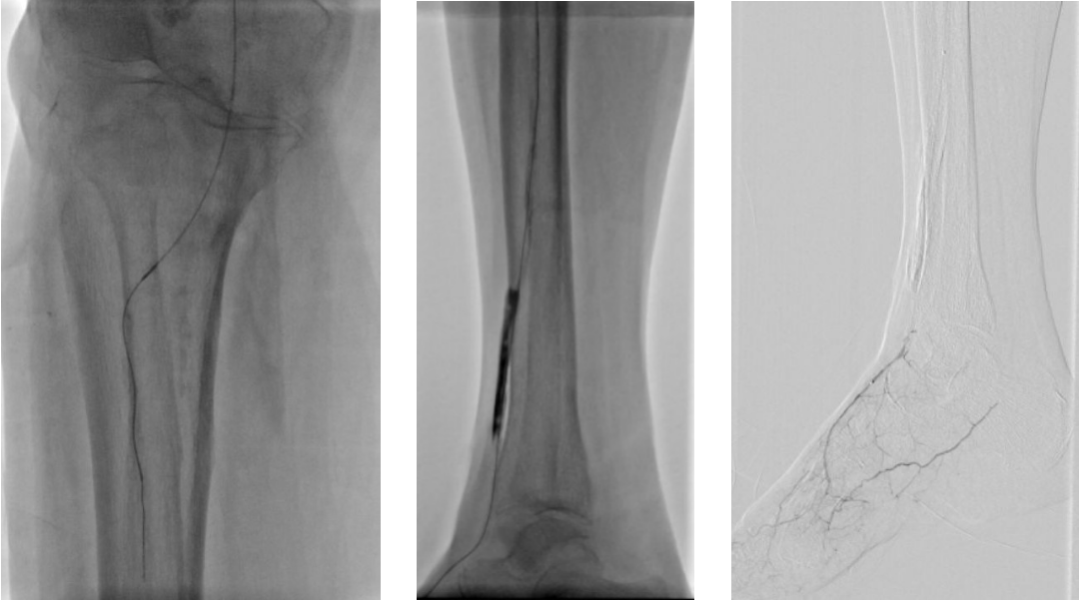

3. 经皮穿刺胫前动脉上段,置入新V18导丝,跟进CXI,与正向的椎管双向会师,建立导丝通路,予以3.0球囊预扩张。

4. 开通胫前-足背动脉

5. 选择6*60mm Shockwave冲击波球囊处理股腘动脉